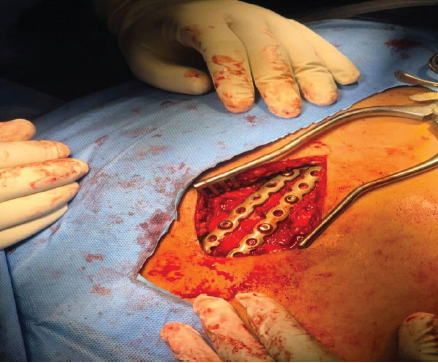

The reduction was stabilized with K-wires. We then decided to use two low-profile 3.5 mm titanium locking plates in a railroad technique, pre-bending them to match the contour of the sternum (Fig. 5).

Figure 5: Railroad technique using prebent 2 low-profile 3.5 mm titanium locking plate fixation of transverse fracture of sternum.

The plates were initially secured with cortical screws, followed by locking screws bicortically, while ensuring that drilling was performed cautiously and checked under thoracoscopy to avoid irritation of underlying structure (Vid). Final reduction was deemed satisfactory and confirmed through fluoroscopy and thoracoscopy. The wound was closed in layers and stapled. The post-operative period was uneventful, and the patient was able to sit upright the following day. Sutures were removed on 12th postoperative day, and follow-up X-rays (Fig. 6) showed that the implants were in good position.